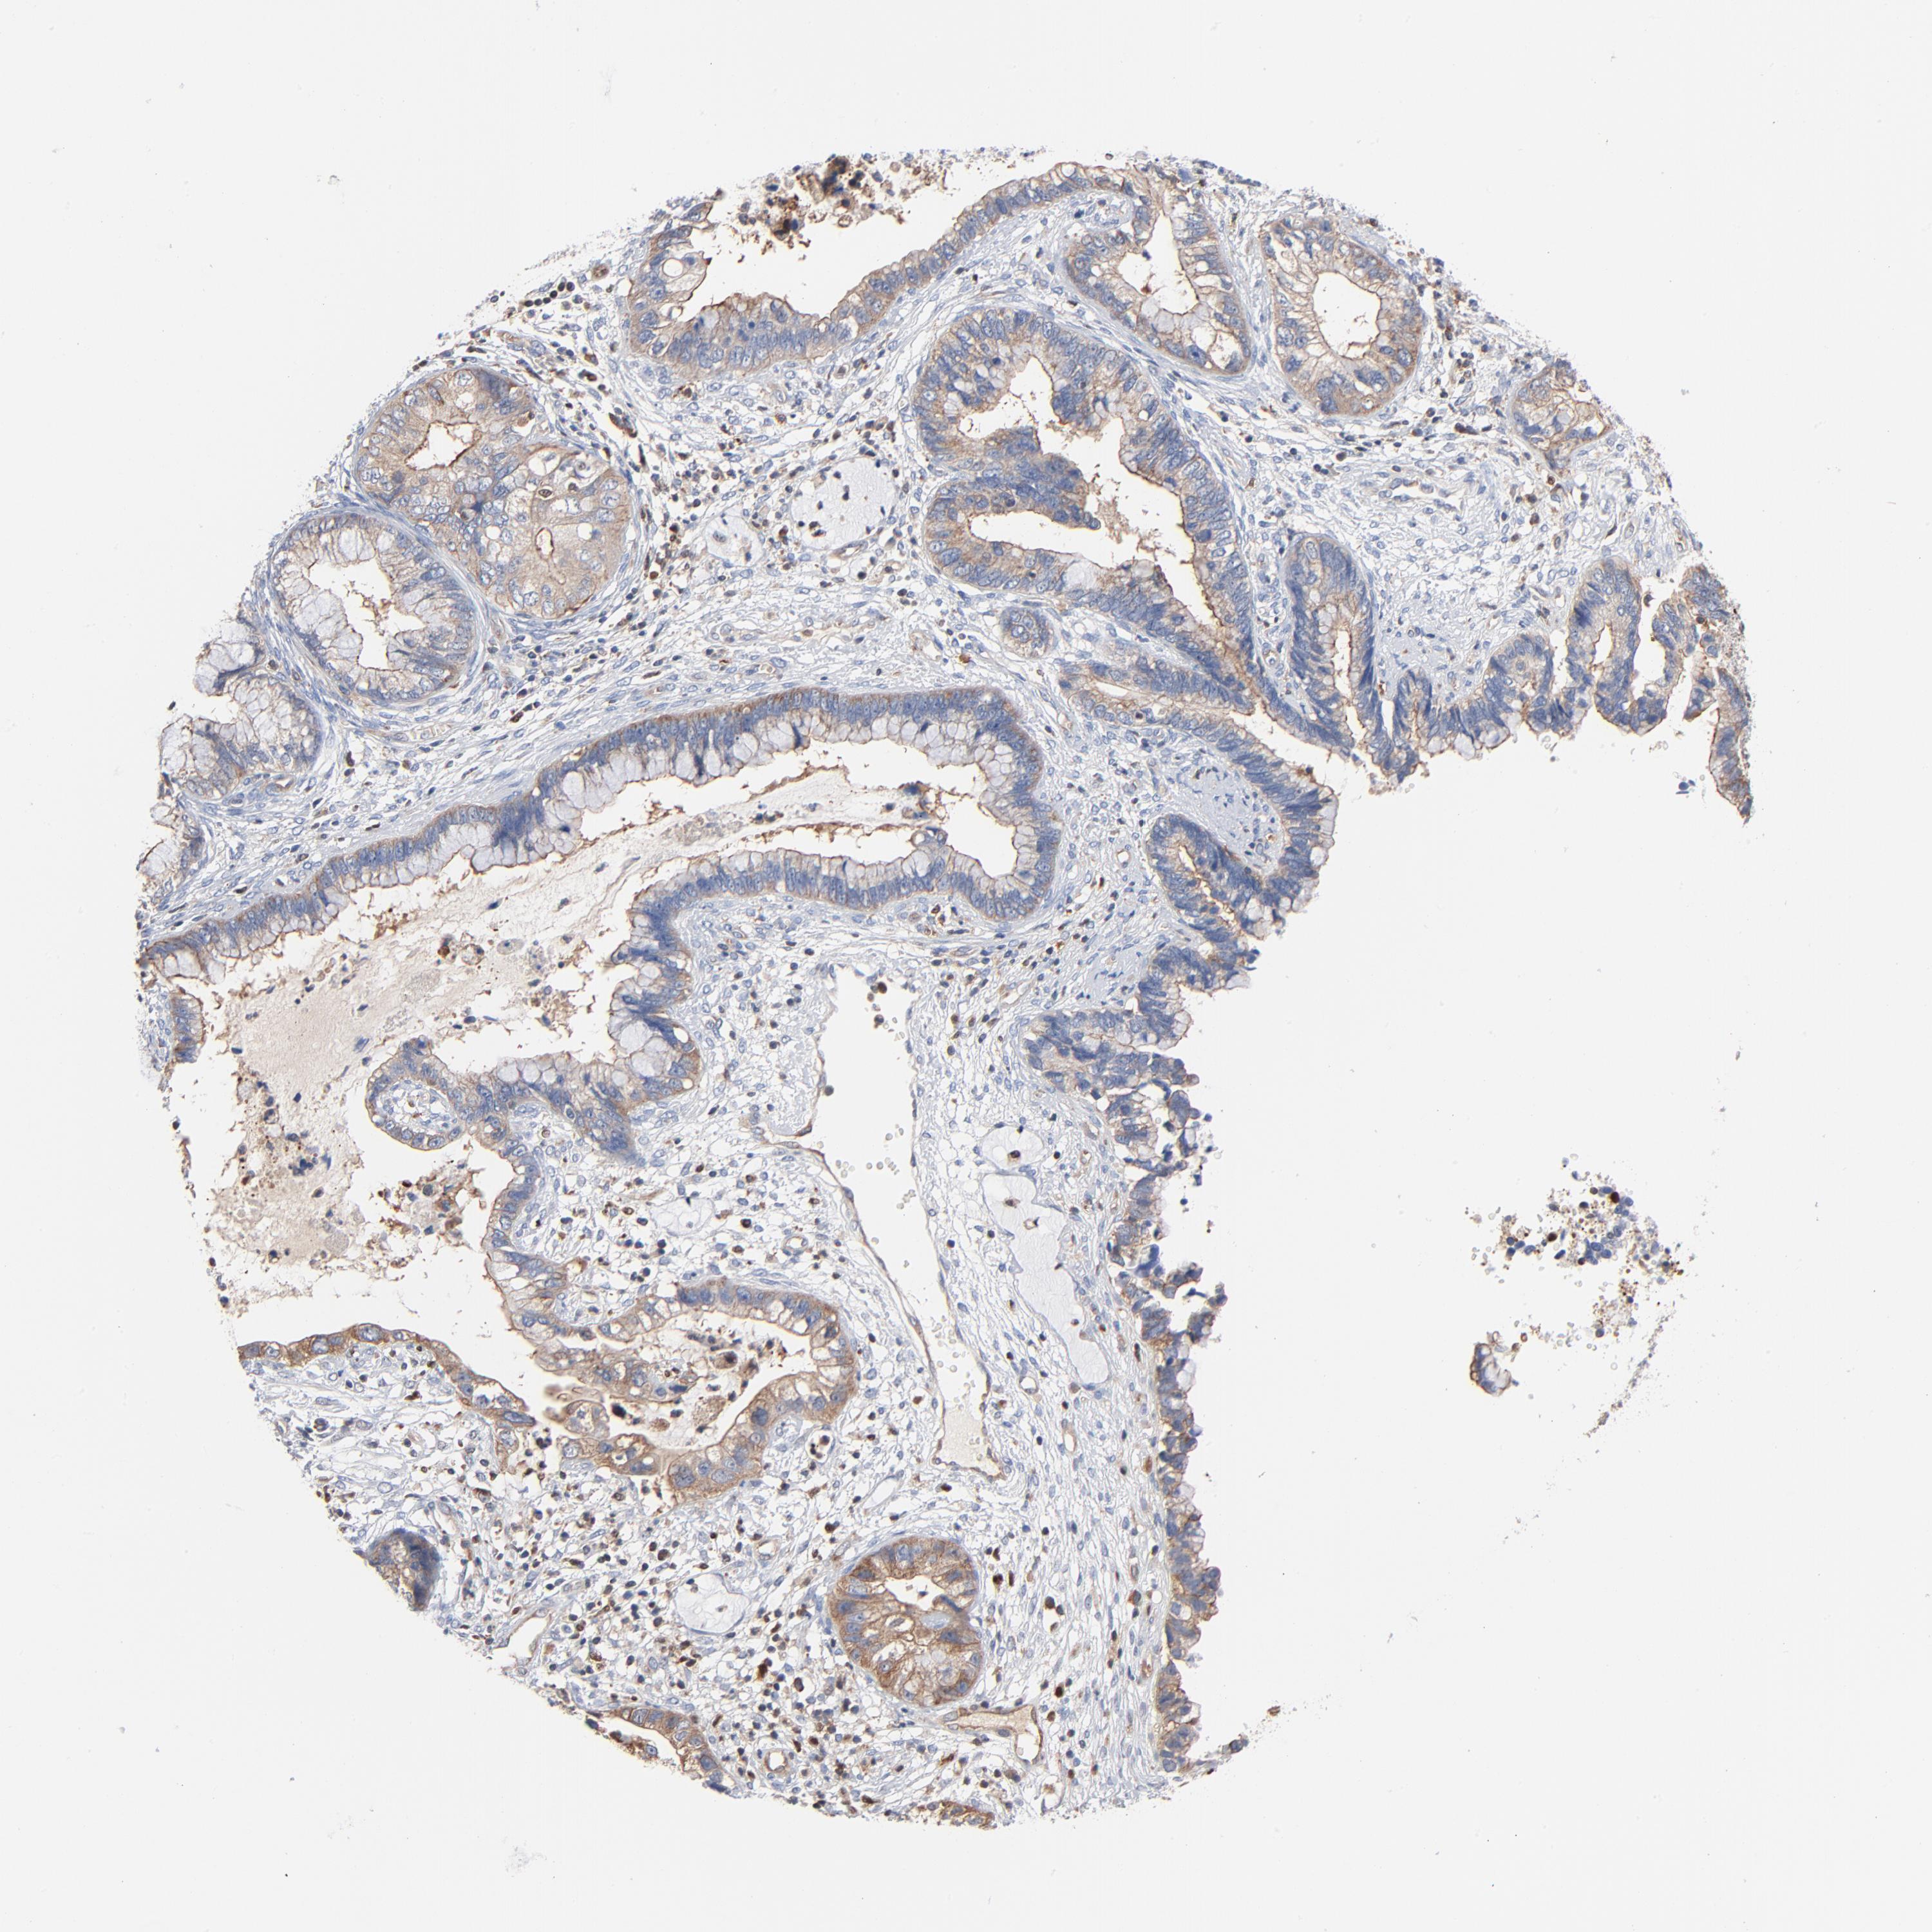

CERVICAL CANCER - Protein expressioni

A mouse-over function shows sample information and annotation data. Click on an image to view it in a full screen mode. Samples can be filtered based on level of antibody staining by selecting one or several of the following categories: high, medium, low and not detected. The assay and annotation is described here.

Note that samples used for immunohistochemistry by the Human Protein Atlas do not correspond to samples in the TCGA dataset.

Antibody stainingi

Antibody staining in the annotated cell types in the current human tissue is reported as not detected, low, medium, or high, based on conventional immunohistochemistry profiling in selected tissues. This score is based on the combination of the staining intensity and fraction of stained cells.

Each image is clickable and will lead to virtual microscopy that enables deeper exploration of all samples and also displays staining intensity scores, fraction scores and subcellular localization as well as patient and tissue information for each sample.

Antibody HPA003578

Staining

High

Medium

Low

Not detected

Intensity

Strong

Moderate

Weak

Negative

Quantity

>75%

75%-25%

<25%

None

Location

Nuclear

Cytoplasmic/membranous

Cytoplasmic/membranous,nuclear

Adenocarcinoma, NOS